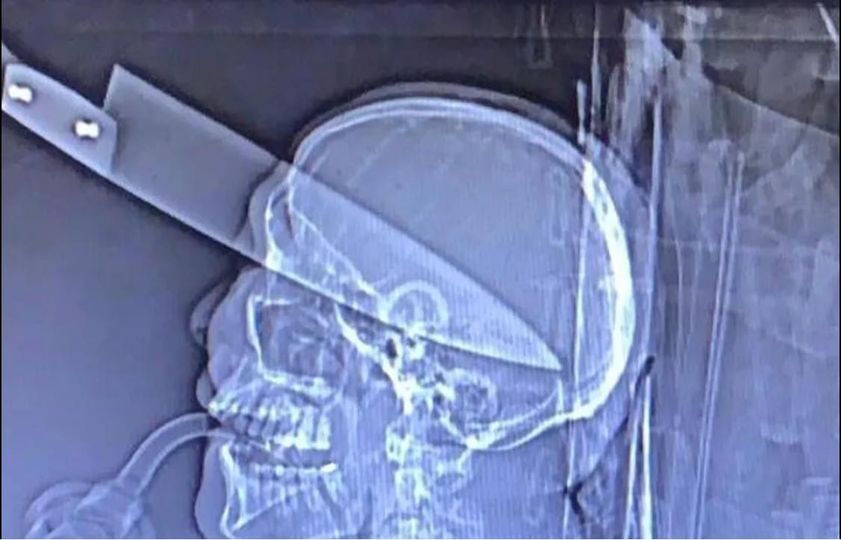

Imediatamente a equipe deslocou ate o local, onde na chegada foi constatado uma mulher que estava com uma da faca cravada no crânio.

Logo em seguida a equipe solicitou apoio a equipe do SAMU devido á gravidade das lesões.

Ele avistou a vitima no canto da escada em uma marquise de uma empresa, ele se aproximou e em posse de uma faca cravou no crânio da vítima e fugiu tomando rumo ignorado.